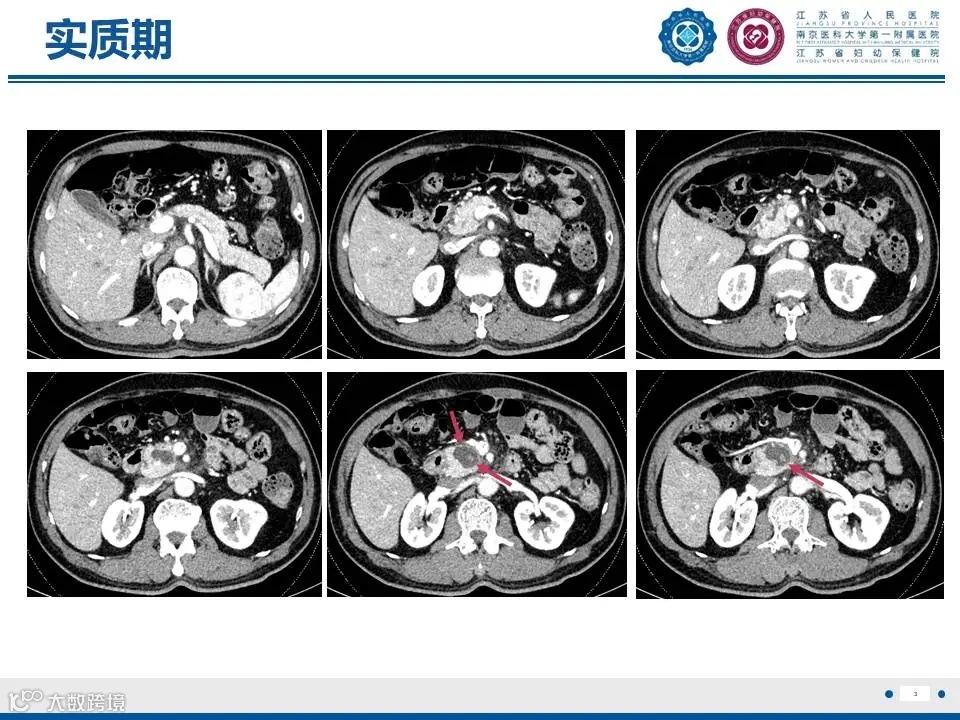

来源:江苏省人民医院放射科